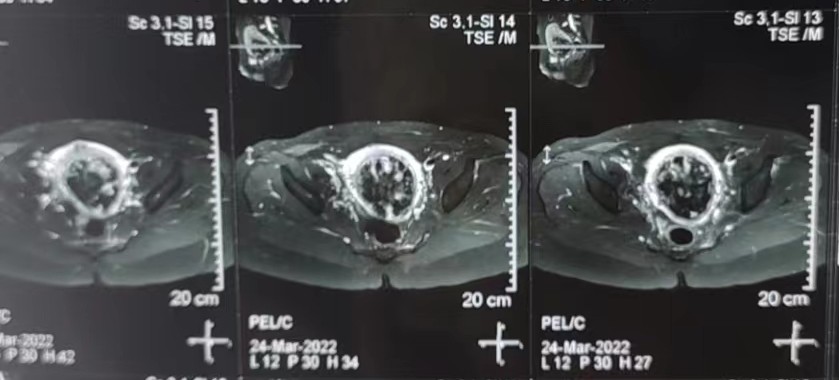

术后清醒后,医生告诉她清宫术中出现大出血,手术无法继续进行,需要继续住院手术治疗。一天后手术室行宫腔镜手术,同样因为大出血无法完成手术操作,后续只能药物辅助治疗。方女士顿觉身心疲惫,遭受一次次的重击,寄望药物治疗能起作用,终结这次不幸的经历。可惜半个月后复查盆腔核磁见宫腔中下部仍有大量组织残留,组织植入宫壁不但界限不清,而且非常血流丰富。

外院复查MR报告

方女士因为子宫后壁的肌层过薄,任何宫腔操作都可能大出血及子宫穿孔可能,见到这样的影像学结果,医生为了方女士的安危也不敢冒然进行下一步的操作。这时候当地医院经治医师考虑可以采用高强度超声聚焦技术治疗,遂推荐患者来暨大附一院就诊。方女士了解到该院妇科多年来进行高强度超声聚焦技术治疗胎盘植入和疤痕妊娠,她抱着希望找到妇科沈媛主任。